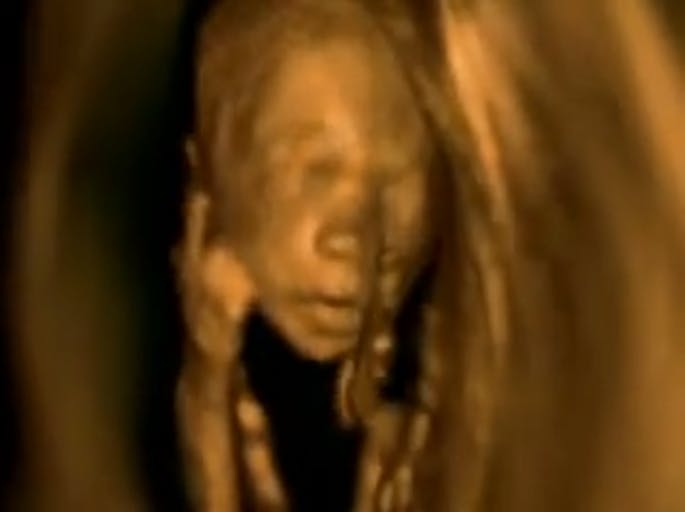

Remarkable 3-D ultrasound video shows humanity of preborn children

This video from a medical diagnostic center in Kiev, Ukraine, shows both early and late fetal development and has been viewed more than 1.4 million times on Facebook. The text states, “What are the babies inside mom. Remarkable video! The video cut through a 3 D Ultrasound.”

These are not clumps of cells. They are human beings exhibiting human behavior in the womb: